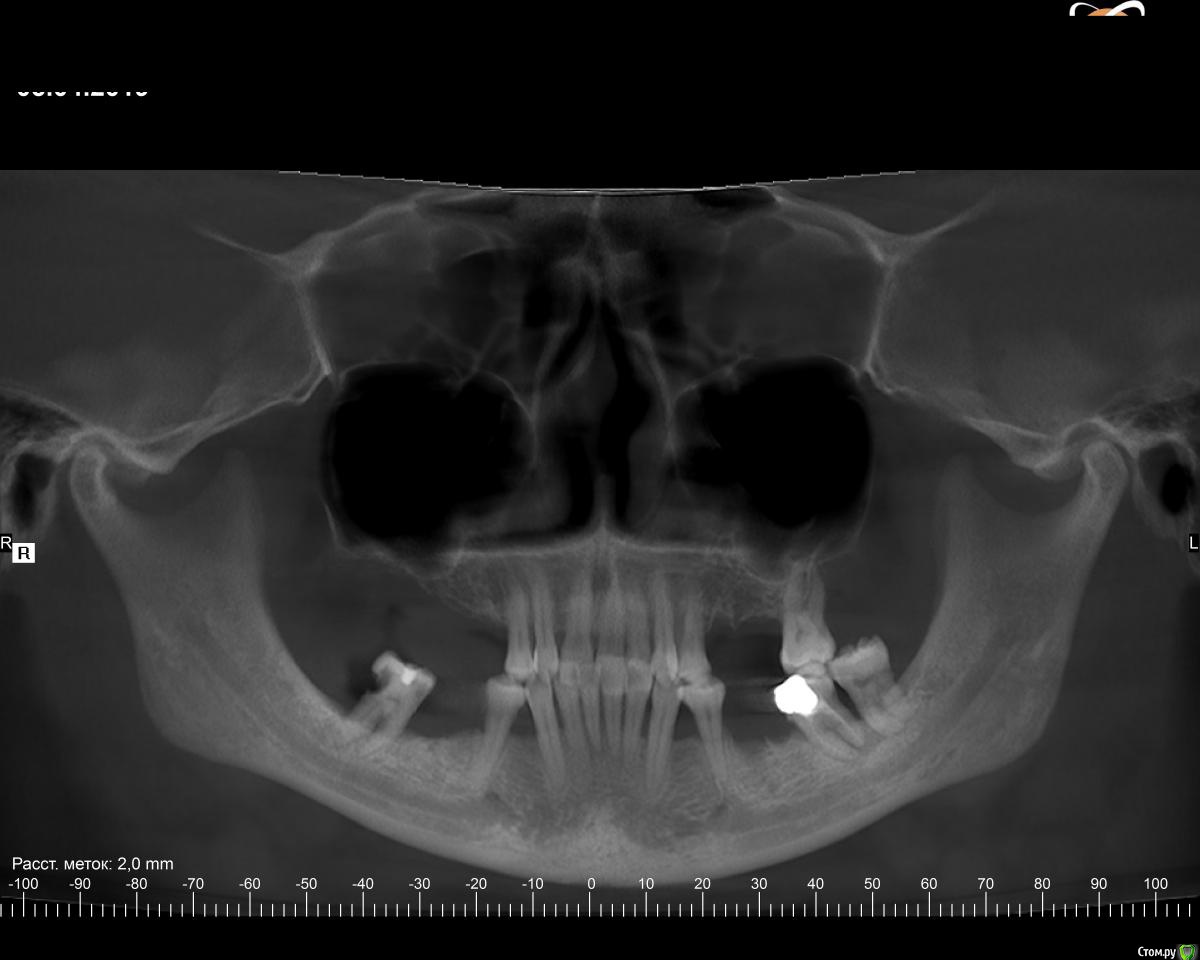

Kristy2 Опубликовано 7 апреля, 2019 Автор Поделиться Опубликовано 7 апреля, 2019 (изменено) все зависит от ситуации. без фотографий трудно что-то посоветовать. (кому-то ставят импланты, а потом брекеты, кому-то наоборот. Потому что разные ситуации, разные задачи)Здравствуйте! Спасибо за ответ Снимок прикрепила Ходила на консультацию к ортодонту. Сказала, ставить брекеты не ранее, чем через полгода, когда десна придут в порядок. Ставить только на верхнюю челюсть, так как снизу десны уже мало у некоторых зубов, шейки оголены. Какую-то лоскутную операцию надо делать вроде как Изменено 7 апреля, 2019 пользователем Kristy2 Ссылка на комментарий